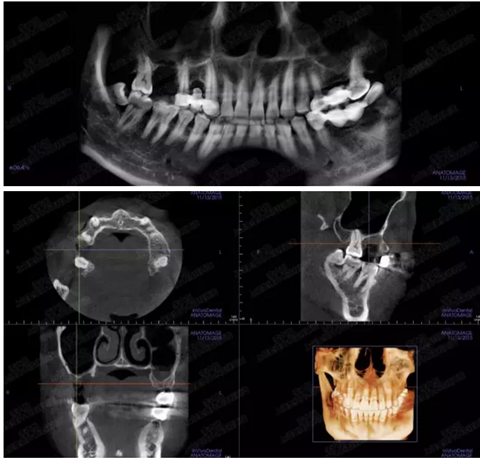

病例二

剩余骨量2mm

003.png

提升10mm

004.png